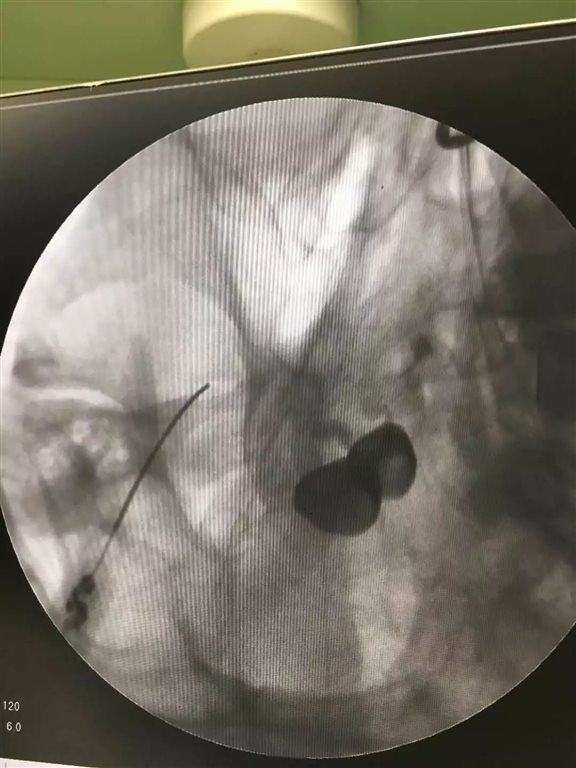

侧位透视,开始测试吧

置入测试电极,0.3V 50HZ感觉测试引出第二支异感,注入无水乙醇0.2ml,

调整测试电极,0.3V 50HZ感觉测试引出第三支异感,运动测试0.7V 2HZ未引出咬肌收缩,注入无水乙醇0.3ml